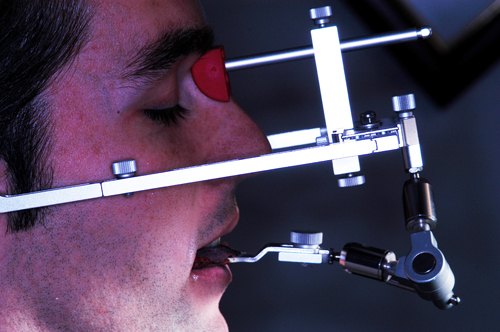

REHABILITACION ORAL MEDIANTE CORONAS DE PORCELANA DE ALTA DENSIDAD Protocolo D.A.T.O. CASO CLINICO: Paciente 24 años, bruxómano, atresia maxilar, referido por ortodoncista para realizar rehabilitación oclusal . Se observa a la inspección la presencia de una hipoplasia adamantina en todos los dientes anteriores, carencia de Guía Anterior , evidentes signos de Facetas Parafuncionales de Desgaste en los posteriores, y una marcada convergencia de los ejes dentarios ápico oclusal, tanto en el maxilar superior como en el inferior, siendo el superior el mas difícil de resolver dado que la inclinación de la Curva de Wilson es inversa a lo que presenta el enfermo. Radiograficamente sin patologías presentes. No presenta movilidades dentarias ni síntomas articulares en las ATM. Debido a la excesiva contractura de su musculatura, se realiza la relajación obviando el uso corriente de las Laminillas de Long, reemplazando el método por un Jig de Lucia el que se deja en boca desde la noche anterior a la cita, advirtiendo al paciente que no debe quitarlo en ningún momento , ya que de hacerlo se repetirían los engramas musculares anómalos que el enfermo presenta. En esas condiciones se toman registros intermaxilares mediante silicona de registros, y se registra el maxilar superior respecto del plano de Frankfort mediante arco facial estático. Se llevan a cabo los encerados correspondientes y se construye en base a ellos el primer juego de provisionales, los que no son cementados debido al perfecto anclaje que presenta. Transcurridos seis meses del uso de provisionales , durante los cuales se ha observado la Oclusión en Relación Céntrica (ORC) inalterable, la ausencia de desgastes patológicos (en las provisorias) y la ausencia de síntomas articulares y musculares, deducimos que el paciente se mantiene en una orto función adecuada, por lo cual comenzamos su rehabilitación definitiva construyendo su Guía Anterior ( determinante primario de la oclusión) en porcelana sobre porcelana de alta densidad.. Observamos los espacios correspondientes en los sectores posteriores y las Disclusiones de los mismos. Los tallados ha sido realizados mediante el concepto de Tallados Gnatológicos, recreados por el Prof. Alvarez Cantoni bajo la denominación de “Preparaciones Racionales”( PREPARACIONES RACIONALES EN PRÓTESIS PARCIAL FIJA. Ed. Hacheace) probando finalmente el trabajo luego de varios días de cementado provisional, y observando la adaptación periférica del borde cavo superficial , su aspecto estético y el importante factor disclusivo : CURVA DE WILSON. y verificando la eficacia lograda mediante una Oclusión Mutuamente Compartida, en la observación de una Disclusión derecha en el Lado de Trabajo y no Trabajo de una disclusión izquierda como así también en la disclusión propulsiva Utilizamos papel de articular de ocho(8) micras para verificar la eficacia de las disclusiones. y de los puntos interoclusales de contacto ANTES DESPUES